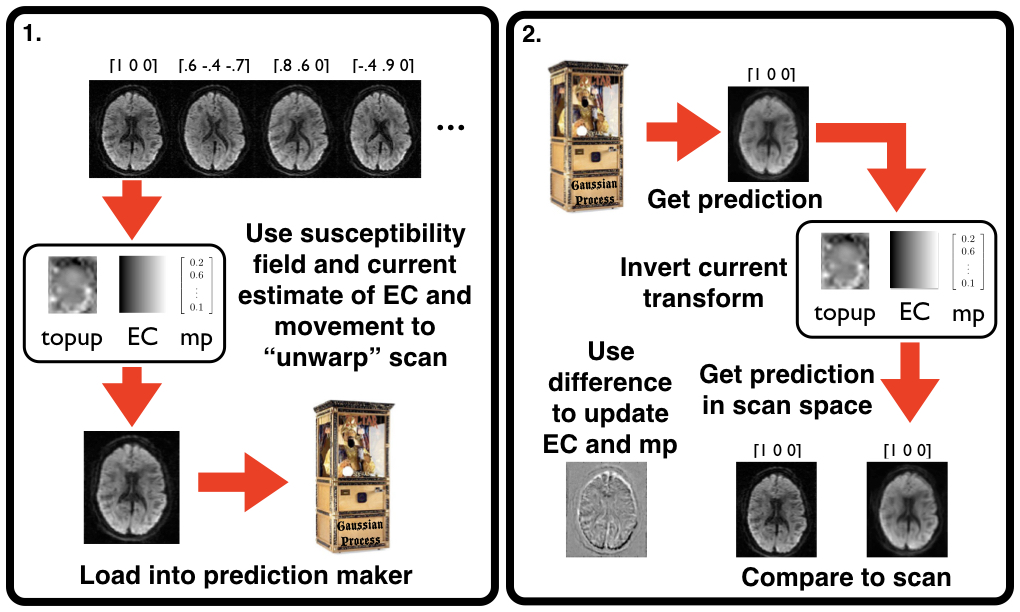

eddy solves this by using a Gaussian Process to make a prediction about what the individual image "should" look like based on all the other images. That way the contrast of the target image will be the same as the image we want to align, and the target image will be in undistorted space if data has been acquired on the whole-sphere or in a less distorted space if it has been acquired on the half-sphere (see below for a discussion about whole- vs half-sphere). A schematic of the process can be seen below.

| Schematic of how eddy works. |

|---|

|

| The eddy registration can be thought of as two steps. 1. The loading step in which the current estimates of EC field, subject movement etc are applied to all the image volumes before being loaded into a Gaussian Process. And 2. The estimation step where a prediction is made for each image volume, the current estimates of correction are "undone" and the resulting image is compared to the observed scan for that diffusion gradient. The difference between the two is what drives the registration. These two steps together comprise one iteration, and `eddy` is typically run for five to ten such iterations. |